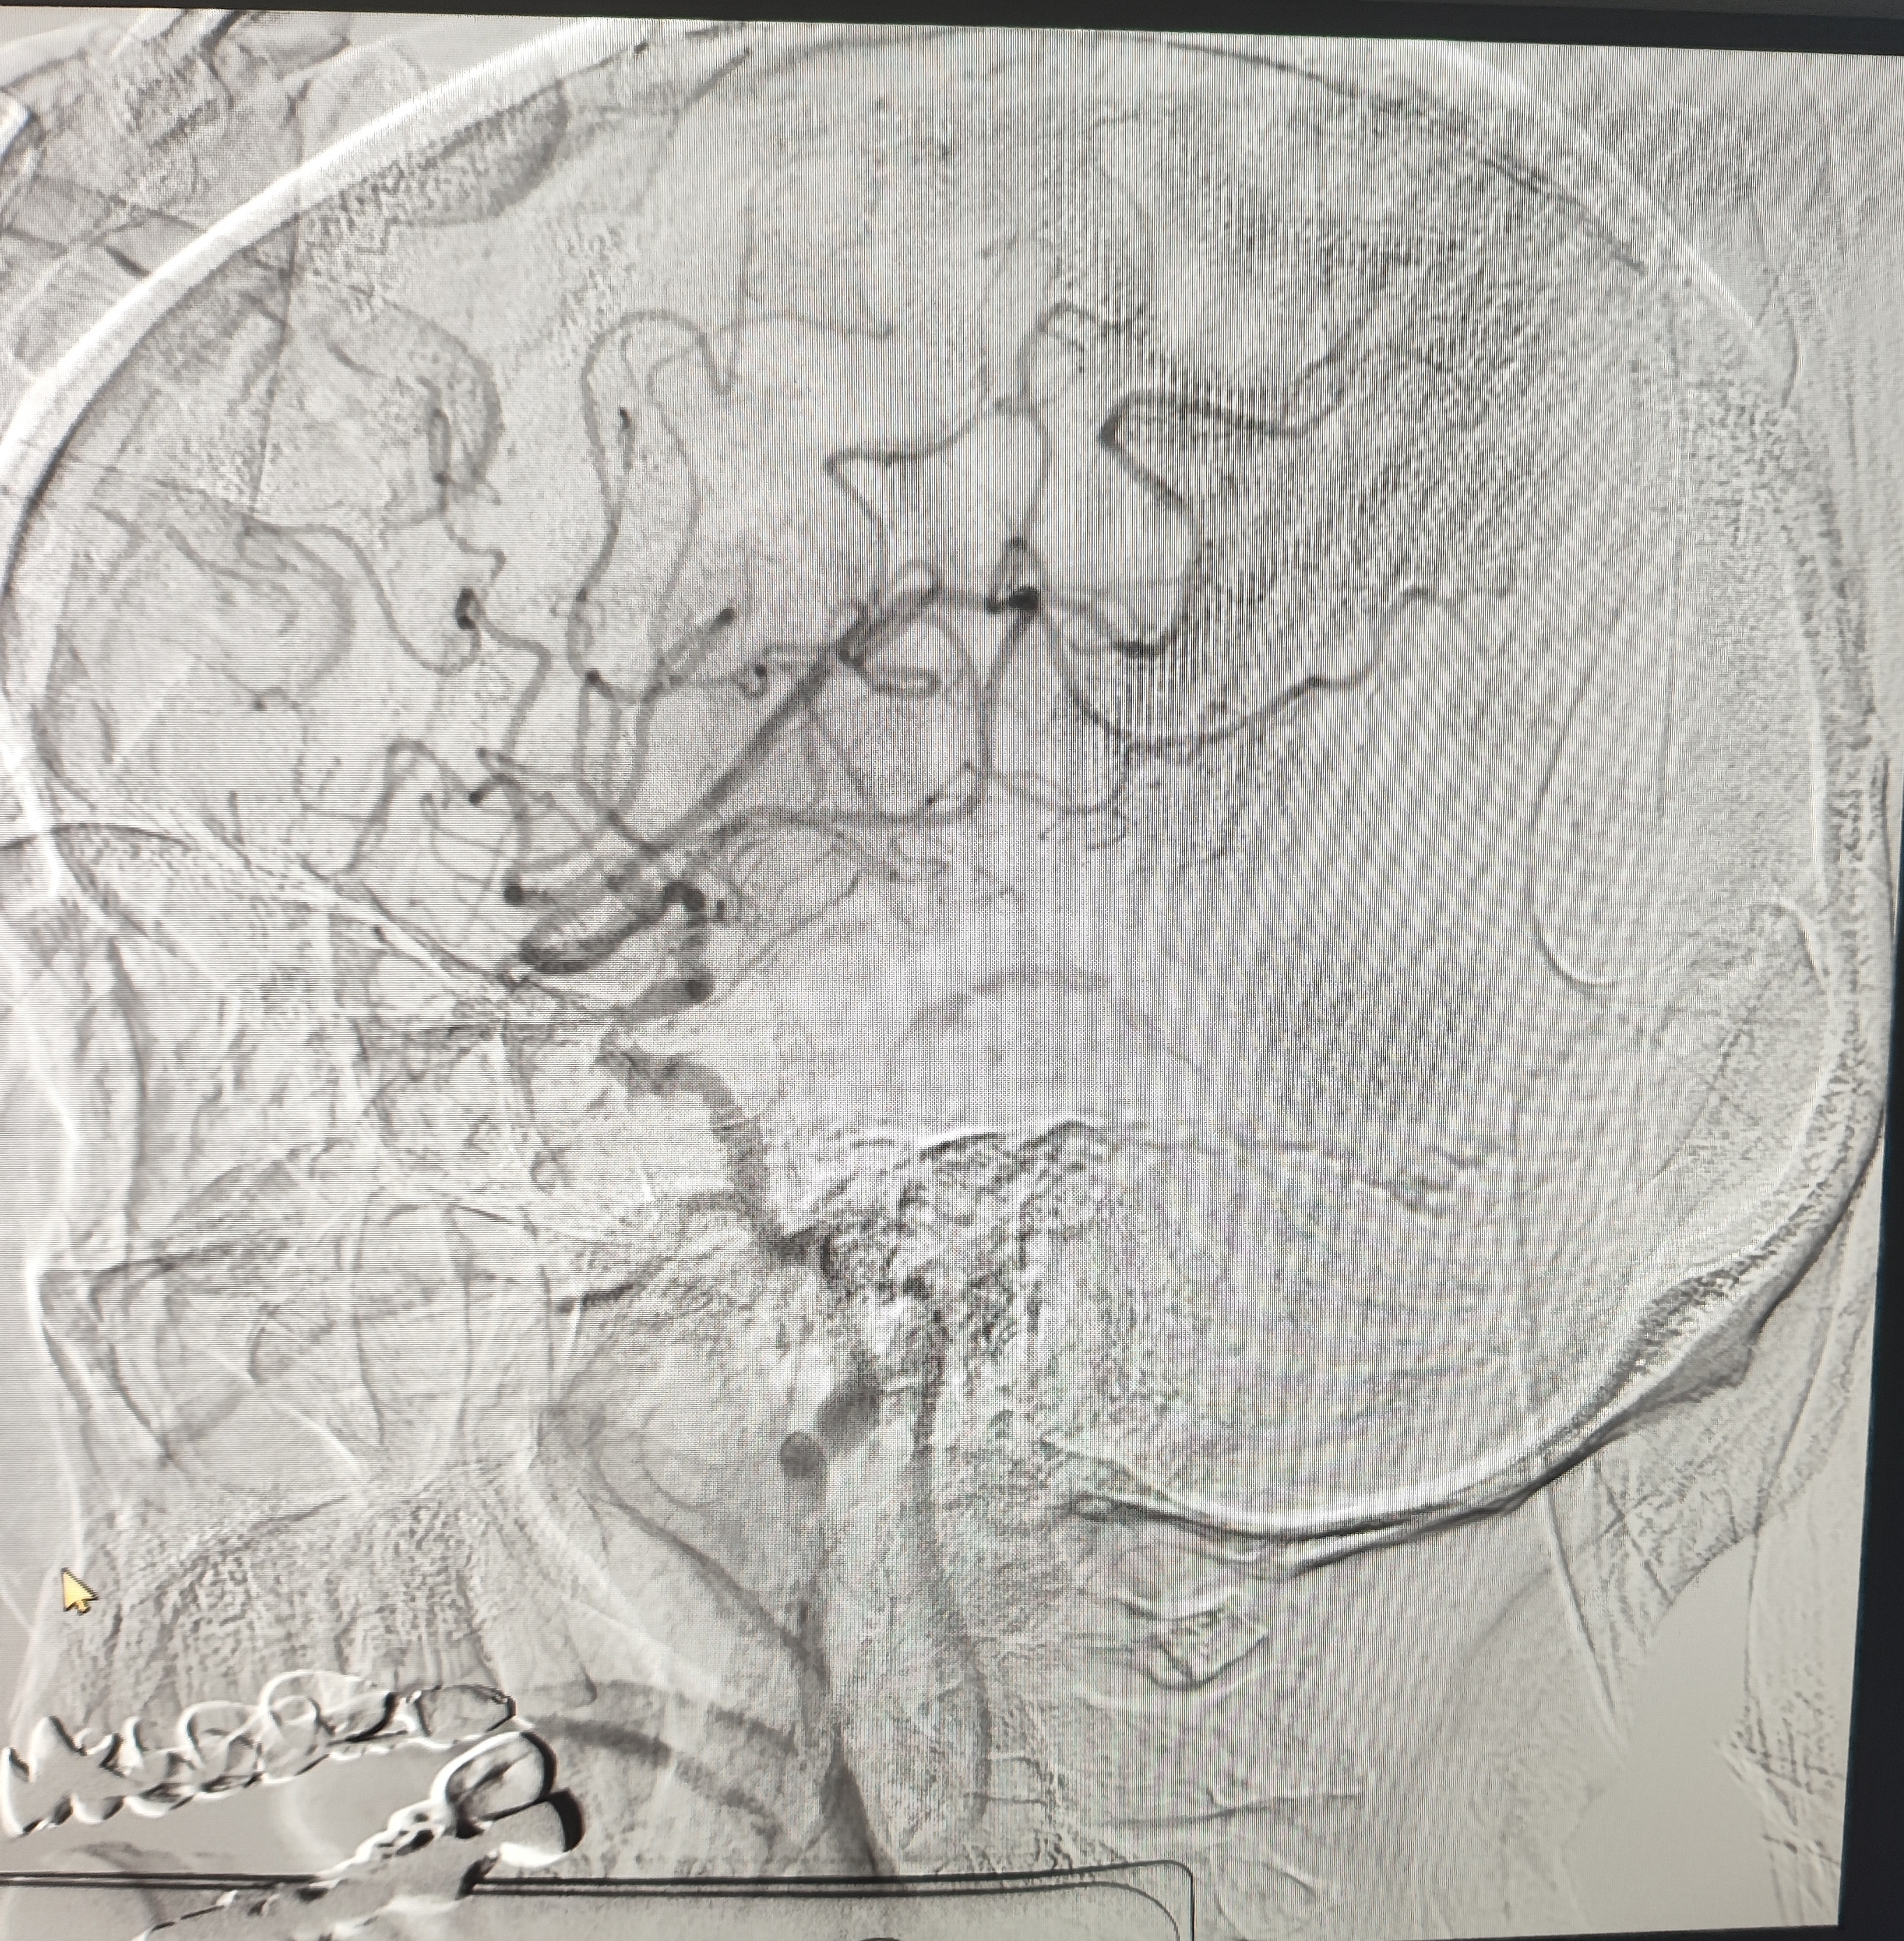

颈总巨大斑块急性闭塞的血管内治疗(双颈动脉支架桥接+支架释放后掉斑块,抽吸取栓)

84岁男性,既往右侧颈动脉狭窄病史8个月,多次脑梗未治疗,本次突发左侧肢体无力来诊,发病30小时后转入我院。

发病当日患者精神差,左侧肢体肌力4级,言语不清晰,左侧鼻唇沟略浅。

症状进行性加重,意识逐渐模糊,烦躁,左上肢肌力1级,左下肢肌力2级,当地考虑开通难度大,转入我院。

急诊上台。